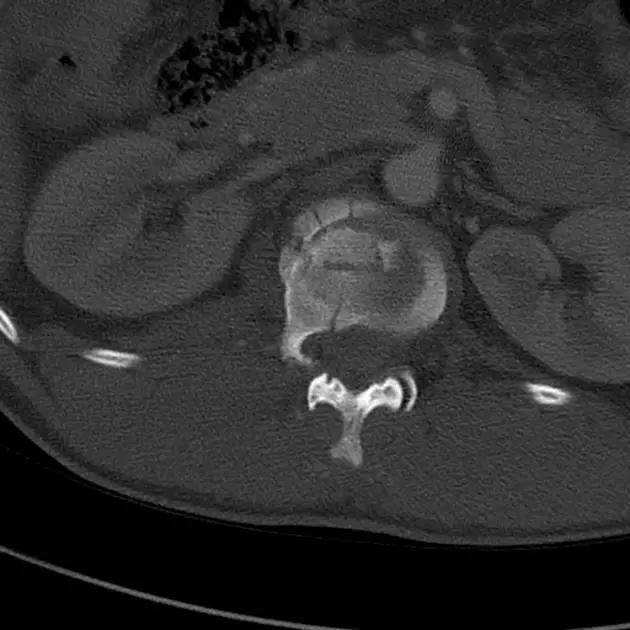

6. Jefferson 骨折

寰椎环的压缩性骨折,骨折是由枢椎压缩性外力引起,骨折多发生在寰椎前侧后侧以及侧方小关节。

第一颈椎双侧性前、后弓骨折,X 线片上很难发现骨折线,有时在正位片上看到 C1 关节突双侧性向外移位,侧位片上看到寰椎前后径增宽及椎前软组织肿胀阴影,CT 检查最为清楚,而 MRI 检查智能显示脊髓损伤情况。

A 图是稳定的 Jefferson 骨折(横韧带完整)轴位像。B 图是不稳定的 Jefferson 骨折(横韧带撕裂)轴位像